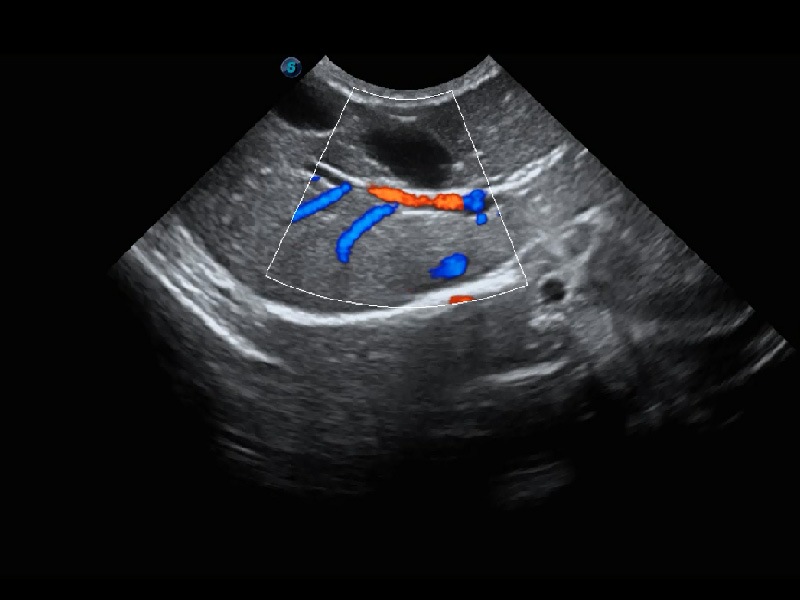

4T血流成像 微察秋毫

融合不同血流成像技术的优势,即可以提升血流成束性,同时可提高血流的视觉敏感性。

PDI 能量多普勒血流

提供高灵敏度和空间分辦率的血流图像,获得更加真实和丰富的诊断信息。

SR Flow 高分辨率血流成像

能够清晰显示细小、低速血流图像,获取传统彩色多普勒技术难以得到的细节和信息。

Bright Flow 立体血流成像

在传统二维血流成像的基础上,呈现血流的立体感,具有动感的生命力之美。精确区分不同血管的空间关系,提高了血流的视觉敏感性。

(犬)四腔心血流

(猫)髂动脉血流频谱

(犬)肾脏血流